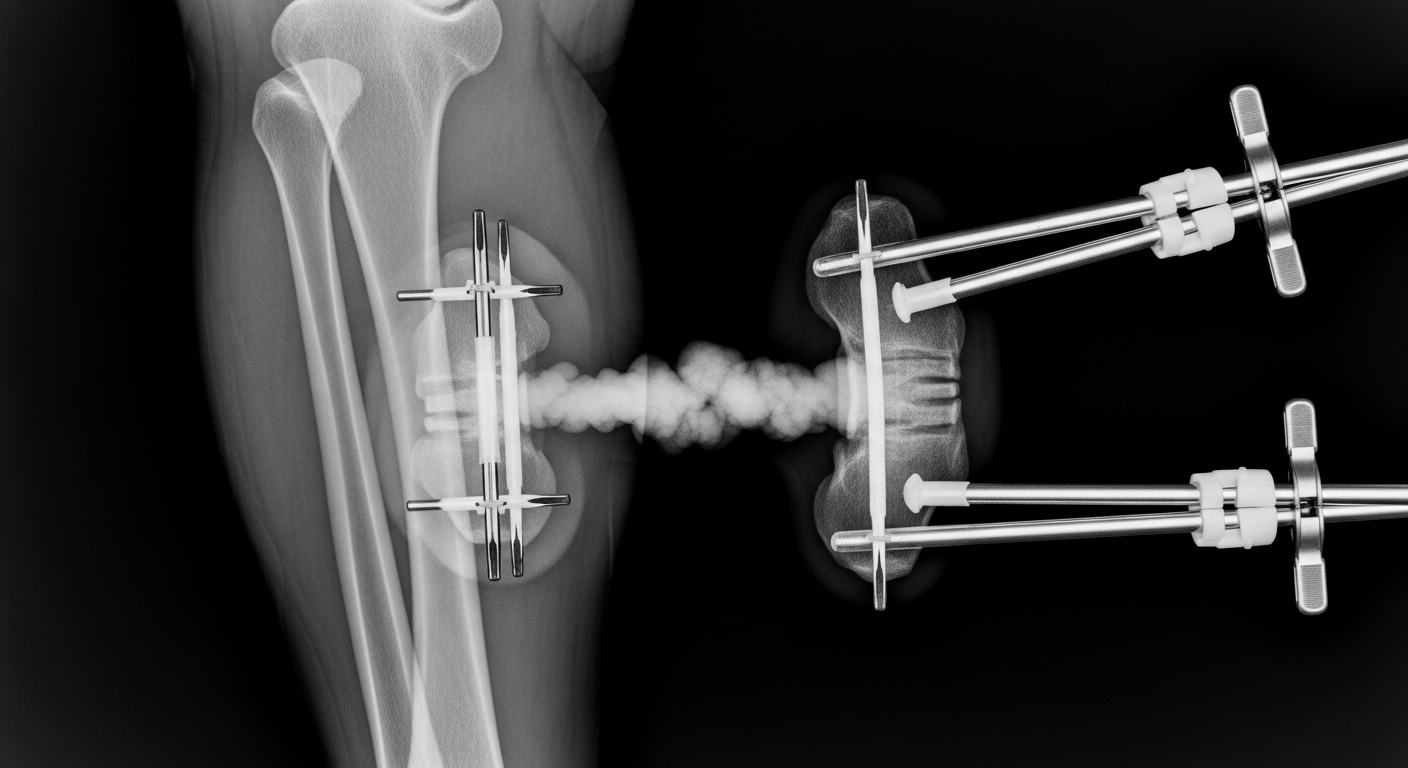

La technique est aussi impressionnante que douloureuse. Les chirurgiens cassent l’os (de la jambe ou du bras) en deux. Ensuite, ils fixent un appareil, un ‘fixateur externe’, de chaque côté de la fracture. Cet appareil est muni de vis que l’on tourne de quelques millimètres chaque jour. Cela écarte très lentement les deux parties de l’os. Le corps, en réaction, va ‘combler’ le vide en créant de l’os nouveau. C’est un processus très long, qui peut durer des mois, et qui nécessite beaucoup de rééducation.